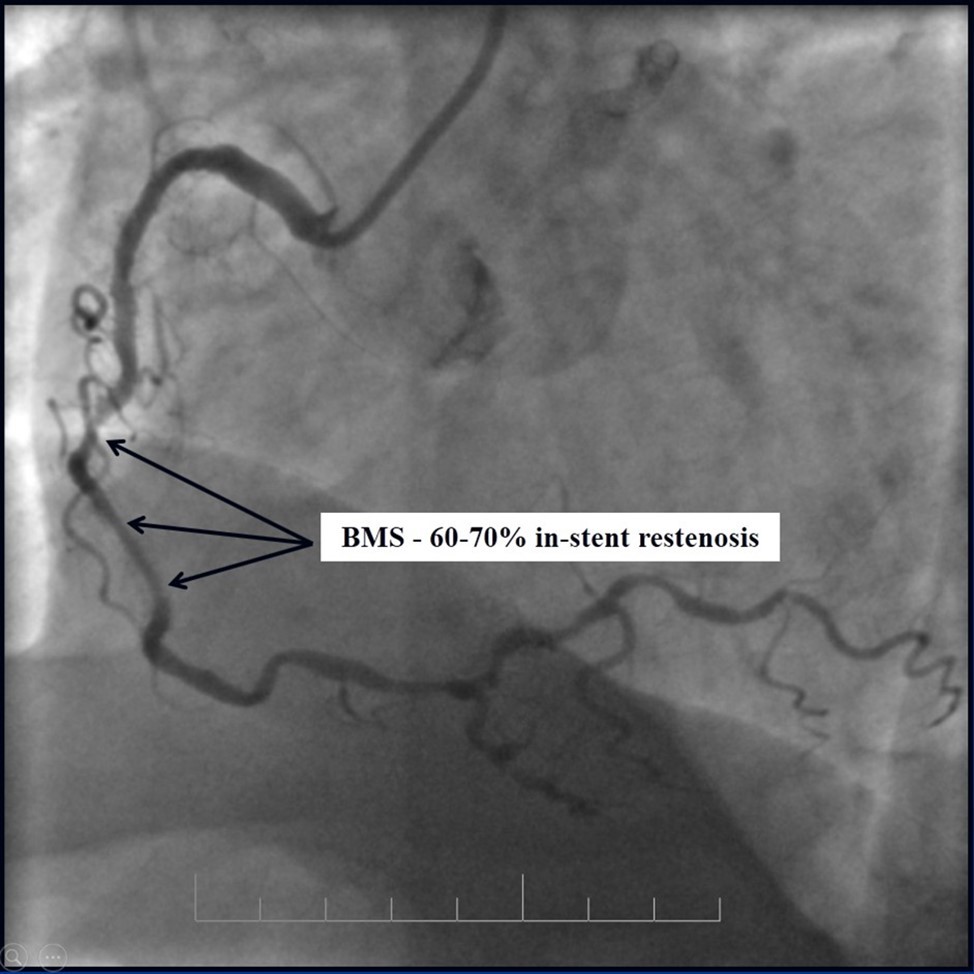

Due to financial problems the second stage was performed after 3 months (during this time the patient solved his financial problems). CAG revealed patent stents in LAD (Figure 7), and 60-70% restenosis by BMS in RCA (Figure 8). In-stent restenosis was treated by plain old balloon angioplasty (POBA), the optimal result was obtained (Figure 9). After LMCA quadrifurcation balloon predilation, 2.5×26 mm DES (Resolute Integrity, Medtronic) was implanted in the IMA, using a modified balloon mini-crush technique. The stent was minimally protruded in the LMCA and its edge was crushed by preloaded MB balloon. Next 2.5×30 mm DES (Resolute Integrity, Medtronic) was implanted in OM1 through the CX (first marginal and circumflex arteries in this particular case have the same ostium). The stent was protruded in the LMCA as in conventional modified balloon crush stenting technique, after stent deployment, its balloon was pulled back and overinflated, then protruded stent was crushed by preloaded MB balloon (Figure 10). 3.5×15 mm DES was implanted in the LMCA so that distal part of the stent covered ostial and proximal segments of the LAD. Sequential post-dilatations were performed using a kissing balloon technique (1. LMCA-LAD-IMA,2. LMCA-LAD-CX-1OM). After post-dilatations, through the stent implanted in CX-OM1, coronary wire and smaller diameter balloon (2.0 mm) were advanced in direction of the CX mid-segment and by balloon dilatation stent’s strut was opened (provisional stenting technique for CX). Finally, the proximal optimization technique was performed in the LMCA using a 3.5 mm diameter non-compliant balloon (Figure 11). The final angiographic image was good, the intervention ended without complications (Figure 11, Figure 12). We could not confirm the result with IVUS or OCT due to several technical and financial problems (not covered by insurance). 1 month after PCI, at regular checkout, the ejection fraction was 48%, the functional class of the Congestive Heart Failure decreased from class II-III to class I and the patient complaints have been disappeared.

Figure 8.RCA, 60-70% in-stent restenosis in BMS

RCA, 60-70% in-stent restenosis in BMS